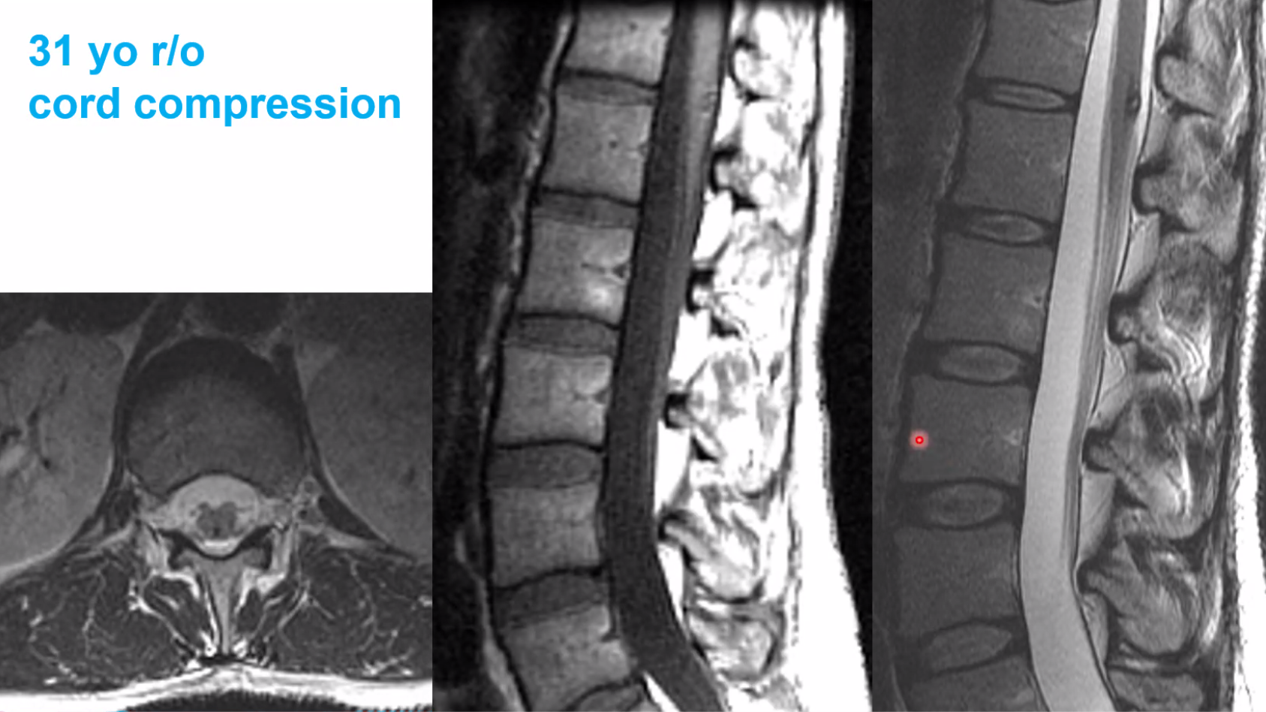

cav mal in the conus medullaris

chocolate covered popcorn

ependymoma would be CENTRAL